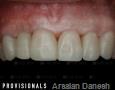

6 Months

7 Months

9 Months